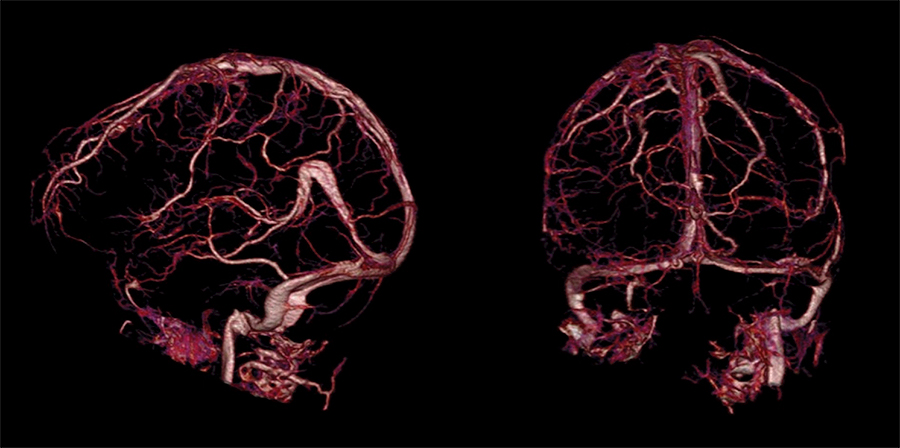

These images show the arteries (red) and veins (green) in the brain of a recent patient with CVST. Before surgery (top images), the arteries (red) are the dominant color but the veins (green) are hard to see because they are so severely occluded. After surgery (bottom images), the veins (in green) are clear, not occluded and are easy to see. Credit: UB Neurosurgery.

After the procedure, CT images showed that all the occluded veins had been opened up.

After the procedure, all the veins (shown in pink and red) are open and visible. Credit: UB Neurosurgery